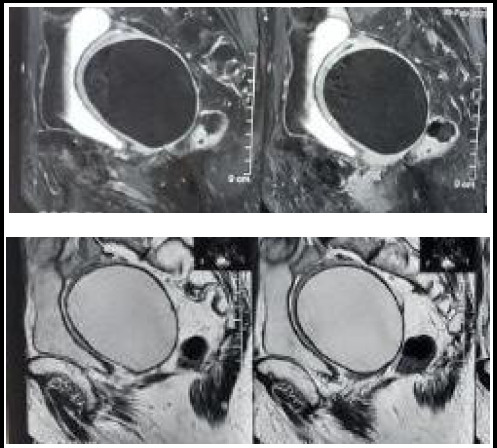

Abstract: Like many agricultural countries, cystic echinococcal zoonotic disease is endemic in Nepal. Incidence of hydatid cyst in liver and lungs are common among the adult population but hydatid cyst of the uterus is an extremely rare entity. We report a case of a 76-year-old menopausal lady who presented with lower abdominal pain for 4 months and underwent laparotomy for provisional diagnosis of myometrial cyst, as shown by MRI scan, however the cyst was found to be primary hydatid cyst of uterus. Postoperatively serological test for hydatid cyst was positive for echinococcus granulosus, further confirmed by histopathological diagnosis. Hence in endemic areas like ours, there should be high index of suspicion of the possibility of hydatid cyst as a differential for cystic pelvic masses.